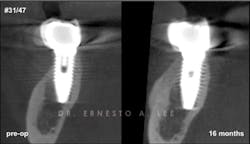

Figure 2: Implant in second molar area was placed 15 years ago. Labial bone remodeled over the years, creating a soft-tissue concavity, and the patient complained of food impaction. Buccal plate regeneration with SMART bone graft exhibits volume stability after 16 months.

Bone augmentation over the exposed implant surfaces has been consistently achieved with the SMART technique. The augmented volumes have remained dimensionally stable, and no symptoms have been reported (figure 2).